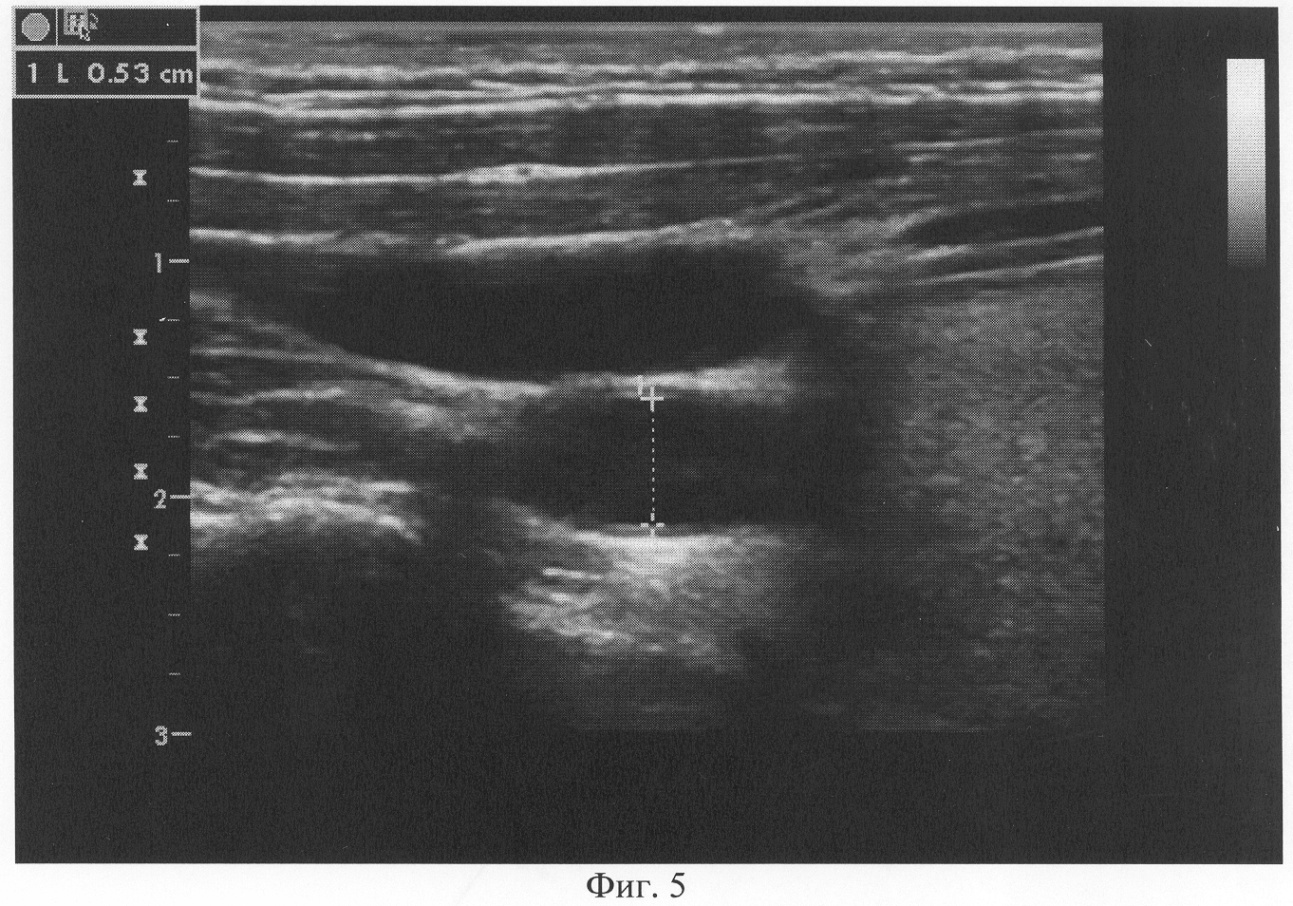

При проведении диагностики предлагаемым способом d равно 10,4% (d0=0,48 см, d1=0,53 см). После купирования симптомов бронхиальной обструкции проведена коронарография. По данным коронарографии правый тип кровоснабжения миокарда, коронарные артерии не изменены. При дальнейшем обследовании на МРТ выявлена грыжа диска Th3-Th4 грудного отдела позвоночника. Таким образом, диагноз ИБС не подтвердился.

Предлагаемый способ поясняется чертежами, где: на фиг.1 показан ультразвуковой датчик с изображением ОСА; на фиг.2 показан диаметр ОСА у больного ИБС (пример 1) до проведения ингаляции сальбутамолом; на фиг.3 – изменение диаметра ОСА после ингаляции сальбутамолом; на фиг.4 показан диаметр ОСА у пациента (пример 2) до проведения ингаляции сальбутамолом; на фиг.5 – изменение диаметра ОСА после ингаляции сальбутамолом; на фиг.6 приведена коронарограмма больного ИБС (пример 1); на фиг.7 – коронарограмма пациента (пример 2).